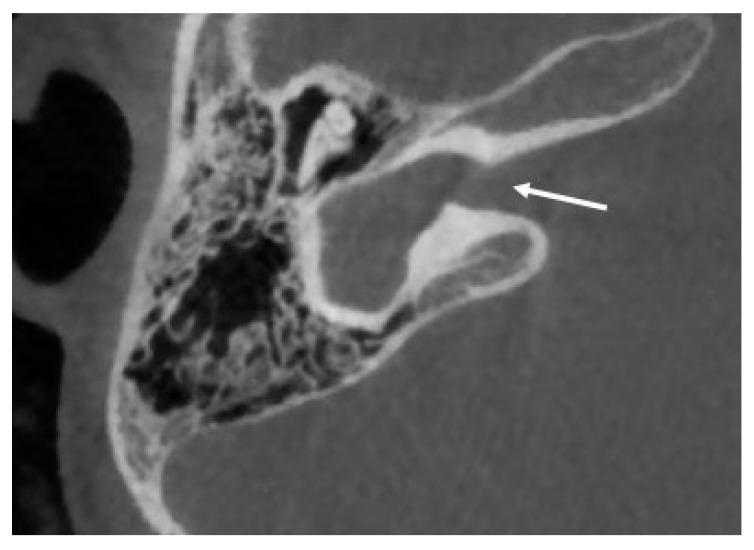

Inner ear malformations are present in 20% of patients with sensorineural hearing loss. Although the first descriptions date to the 18th century, in recent years the knowledge about these conditions has experienced terrific improvement. Currently, most of these conditions have a rehabilitative option. Much less is known about the etiology of these anomalies. In particular, the evolution of genetics has provided new data about the possible relationship between inner ear malformations and genetic anomalies. In addition, in syndromic condition, the well-known presence of sensorineural hearing loss can now be attributed to the presence of an inner ear anomaly. In some cases, the presence of these abnormalities should be considered as a characteristic feature of the syndrome. The present paper aims to summarize the available knowledge about the possible relationships between inner ear malformations and genetic mutations.